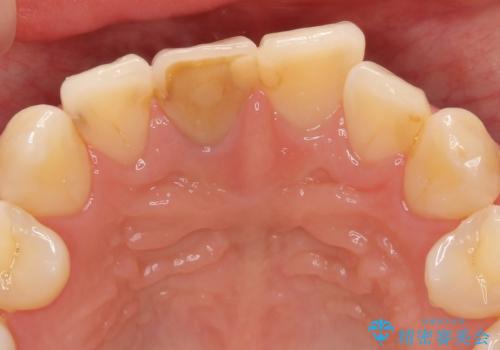

前歯の変色 根管治療と高品質セラミック歯科治療

- 前歯の変色の改善を求めて来院されました。

X線検査を行ったところ、共に深い虫歯が原因となり神経が死んでしまっている状態であることがわかり、根管治療を行ったのちセラミック補綴を行っていくこととなりました。